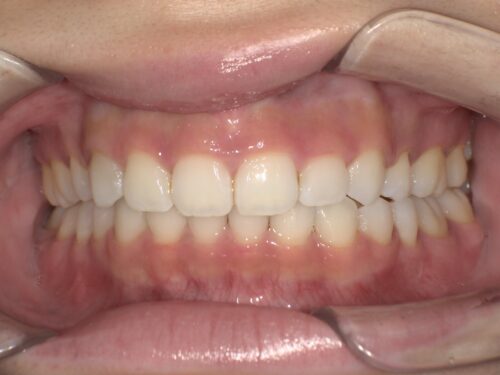

治療後・正面の写真

パッと見た時の印象が違いますよね。前歯の出っ張りが改善され、歯並びがきれいに整っています。